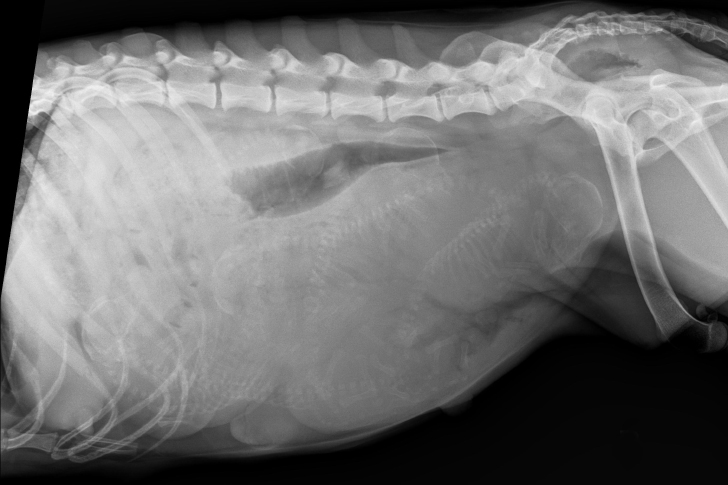

When Dr. Greene moved to the X-ray machine, he hoped it would ease his growing unease. But as the screen lit up, his eyes widened. The X-ray showed tiny forms packed into Lola’s belly like sardines in a can. Not only were there more puppies than usual, but their size suggested this wasn’t just a large litter.